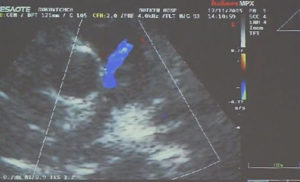

Надежный диагноз коронарной фистулы ставится только после коронарографии. Зондирование полостей сердца не выявляет порока, а указывает только на наличие лево-правого шунта при фистулах в правых отделах. Точный диагноз может быть поставлен с помощью двухмерной и допплер-ЭхоКГ.

В связи с характером шума может быть ошибочно поставлен диагноз ОАП, ДМЖП с аортальной недостаточностью, аортолегочного свища, разрыва аневризмы синуса Вальсальвы, артериовенозных свищей легких. С этими пороками следует проводить дифференциальную диагностику.